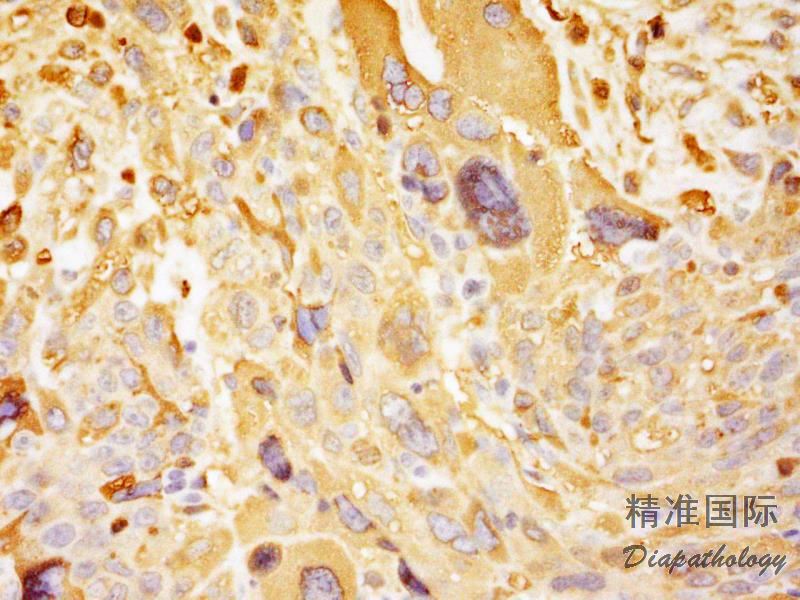

免疫组织化学染色:

合体滋养层细胞表达 hCG、hPL、Glypican3. inhibin 和 EMA,中间型滋养层细胞弱表达 hPL,细胞滋养层细胞表达 SALL4. GDF3. P63. GATA3。